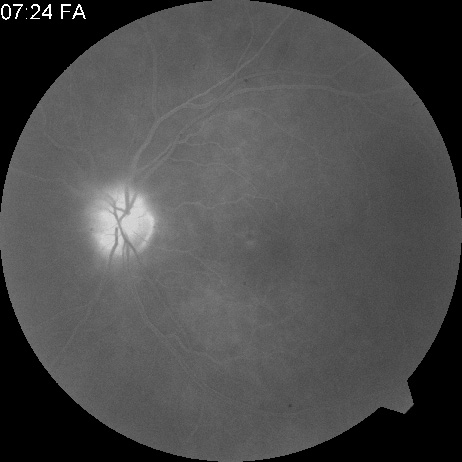

Ophthalmic artery obstruction is characterized by an initial opacification of the entire retina in a manner similar to that of central retinal artery obstruction (Fig. 4A). The cherry-red spot may or may not be present, however.119 The difference between an ophthalmic artery obstruction and central retinal artery obstruction is that in an ophthalmic artery obstruction, with time, optic atrophy develops, as does varying amounts of pigmentation due to the lack of perfusion of the retinal pigment epithelium (see Fig. 4D). This pigment is generally diffusely scattered throughout the posterior pole but it may also be seen in greater amounts in the periphery.

Intravenous fluorescein angiography generally shows moderate to marked abnormalities in the filling of the choroid, in addition to a delay in filling or even nonfilling of retinal vessels (see Fig. 4B and 4C). Staining of the retinal pigment epithelium can also be seen; this staining either can occur locally in the macular area or it can be diffuse.119 The electroretinogram shows abnormalities of both a- and b-waves, reflecting ischemia to both the inner and outer retina. Almost all reported patients have had an initial visual acuity of no light perception; virtually no patients can be expected to have a final visual acuity better than that.119 An acuity of no light perception is a clue to the presence of an ophthalmic artery obstruction. Because relatively few patients with central retinal artery obstruction have an initial visual acuity of no light perception, no light perception usually suggests the likelihood of some obstruction of the choroidal circulation.14